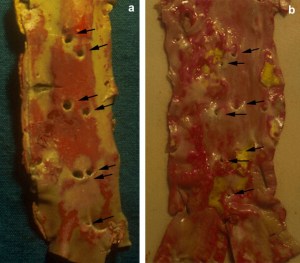

Atherosclerosis can cause disc degeneration, and consequent back problems, by obstructing the blood vessels which feed the lumbar spine.[vii] The autopsy and angiography results below show normal (a), and cholesterol-clogged (b) lumbar arteries and their openings in the wall of the abdominal aorta.[viii]

Figure 3: (a) Well-preserved and (b) stenotic orifices of the 2nd–4th lumbar arteries in the posterior wall of the abdominal aorta. Red staining shows fatty streaks.[x] © 2009 European Society for Vascular Surgery